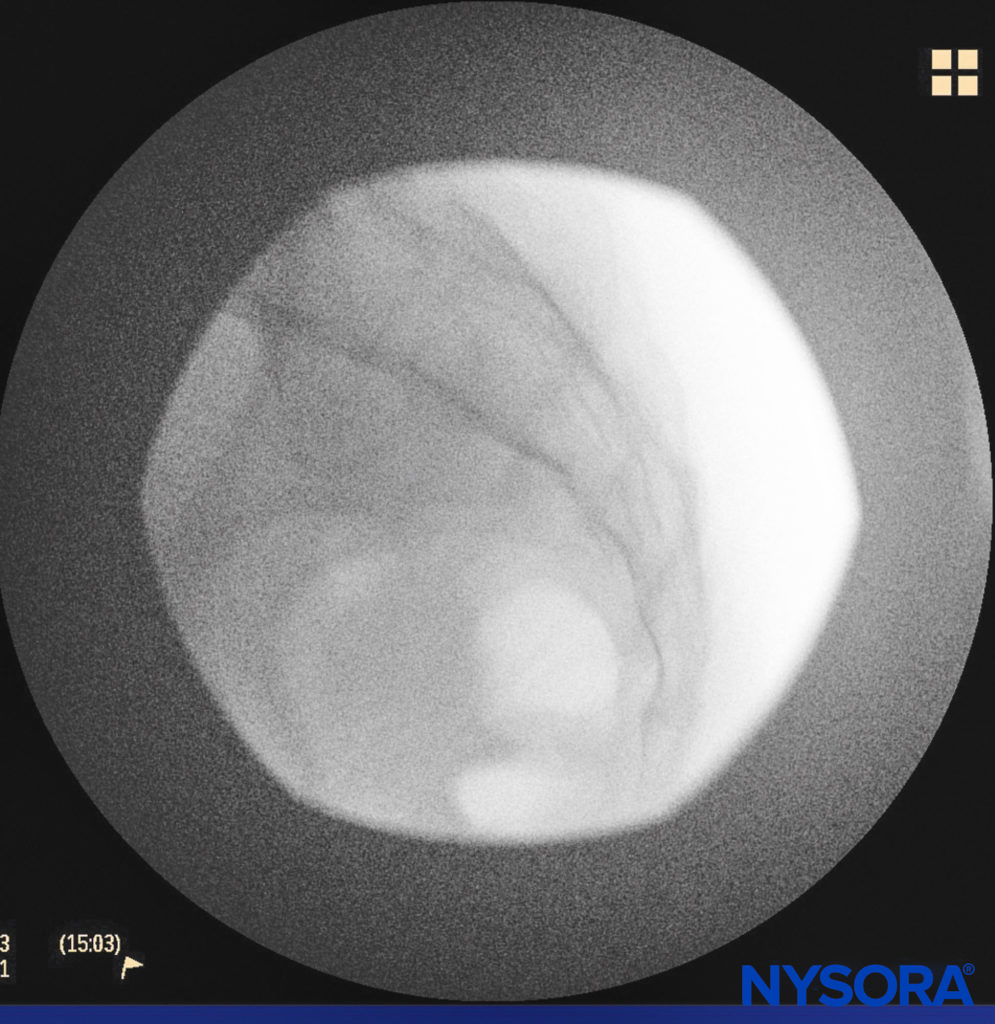

A small-gauge 1.5-inch needle is then utilized to infiltrate the skin over the sacral hiatus using 3-5 mL of 1%-1.5% plain lidocaine HCl (Figure 3). If fluoroscopy is utilized, a lateral view is obtained to demonstrate the anatomic boundaries of the sacral canal. We routinely leave the local anesthetic infiltration needle in situ for this view because it demonstrates whether the approach is at the appropriate level for subsequent advancement of the epidural needle. With fluoroscopy, the caudal canal appears as a translucent layer posterior to the sacral segments. The median sacral crest is visualized as an opaque line posterior to the caudal canal. The sacral hiatus is usually visualized as a translucent opening at the base of the caudal canal. The coccyx may be seen articulating with the inferior surface of the sacrum (Figure 4).

FIGURE 4. Lateral fluoroscopic image demonstrating the boundaries of the caudal canal.